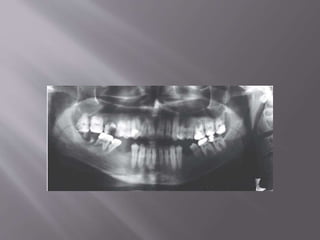

 A panoramic radiograph and tracing together

with the periapical radiographs revealed extensive

apical root resorption in all teeth except teeth 18,

23, 31–34, 37and 41–44. Eighteen teeth had apical

root resorption, mostly in the maxilla

 On the basis of the history, clinical examination and

radiographic evaluation, a diagnosis of multiple

idiopathic apical root resorption was made.